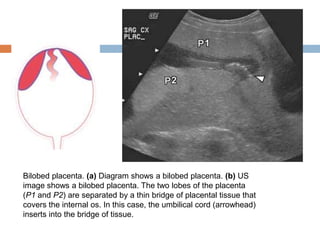

Bilobed placenta. (a) Diagram shows a bilobed placenta. (b) US

image shows a bilobed placenta. The two lobes of the placenta

(P1 and P2) are separated by a thin bridge of placental tissue that

covers the internal os. In this case, the umbilical cord (arrowhead)

inserts into the bridge of tissue.

Bilobed placenta. (a)Diagram shows a bilobed placenta. (b) US image shows a bilobed placenta. The two lobes of the placenta (P1 and P2) are separated by a thin bridge of placental tissue that covers the internal os. In this case, the umbilical cord (arrowhead) inserts into the bridge of tissue.